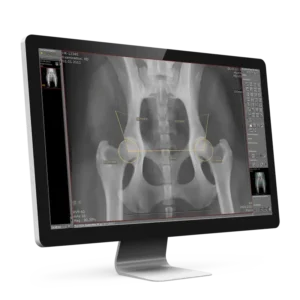

1. Direct Radiography (DR)

Direct Radiography X-ray (DR) systems provide fast, high-resolution imaging for small and large animals. With advanced detectors and immediate image access, DR systems help veterinarians make accurate diagnoses efficiently. Integrated with dicomPACS® and ORCA® Cloud by OR 4Vet, these solutions optimize workflow in every veterinary clinic.